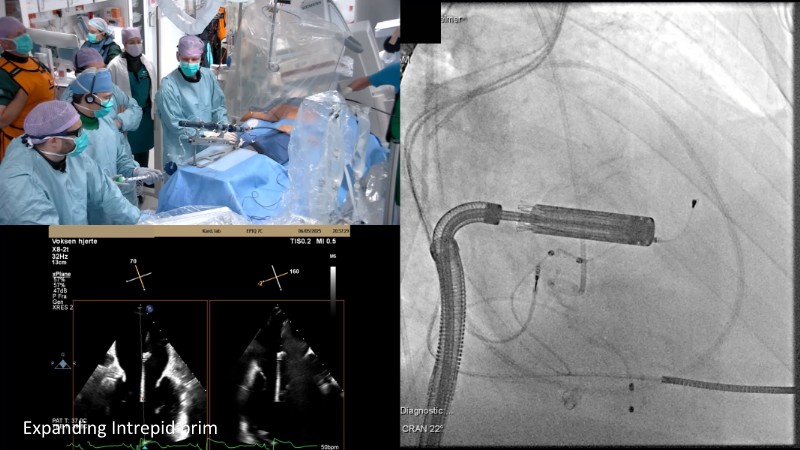

This EuroPCR 2025 session highlights the evolving role of transcatheter mitral valve replacement, focusing on the clinical potential of mitral regurgitation elimination. Get an overview of the current status of the Intrepid TMVR programme, learn about the transition to the 29Fr transfemoral system, and explore how patient screening—especially in the presence of mitral annular calcification—impacts procedural planning. Real-world case reviews from the APOLLO-EU trial offer practical insights into how this next-generation system is being applied in Europe today.